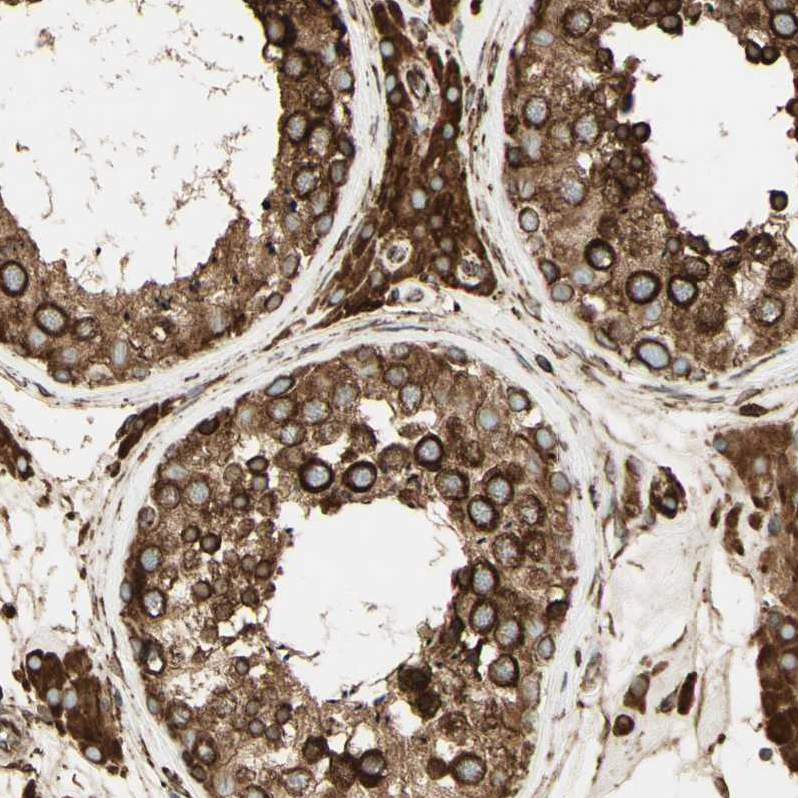

Immunohistochemical staining of human cerebral cortex, placenta, testis and tonsil using Anti-CANX antibody HPA009433 (A) shows similar protein distribution across tissues to independent antibody HPA009696 (B).